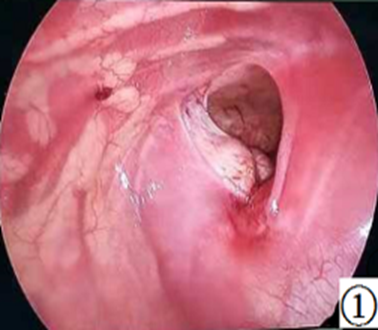

说了这么多,膈疝应该怎么治疗呢?方法只有一个——手术修补缺损,让腹腔和胸腔完全分开,泾渭分明,井水不犯河水,把空间还给肺,让它有机会能好好生长,好好工作。目前膈疝的主流手术方法是从胸腔内修补膈肌缺损,很多情况下可以做微创手术。修补的时候绝大多数可以直接使用已有的膈肌组织用针线缝合修补。但对于缺损较大的膈疝可能需要使用补片,就像女娲补天需要用五彩石一样。那手术风险大吗?其实新生儿做手术风险都有些大的。一般的同样的手术,和婴儿相比,新生儿手术的风险很大一部分来自麻醉。新生儿对买醉药代谢慢,买药作用容易蓄积,为了维持麻醉状态一般都会根据手术时间调整麻醉药的用量。其次,新生儿的体表面积体积比较大,在手术中容易丢失热量导致体温下降。因此可以看出,手术时间越长,风险是越大的。传统的膈疝修补需要一针一针的缝合,一般时长需要近2小时。而目前我们治疗先天性膈疝采用新型的微创手术,胸腔镜下修补膈疝,用编织线结扎修补膈肌的缺损,就像扎麻袋口一样,手术时间可缩短至20分钟左右,可以大大降低手术麻醉带来的风险,对组织的创伤小,对肺影响小,手术切口基本可达到无痕的水平,大大加快了膈疝术后的恢复。